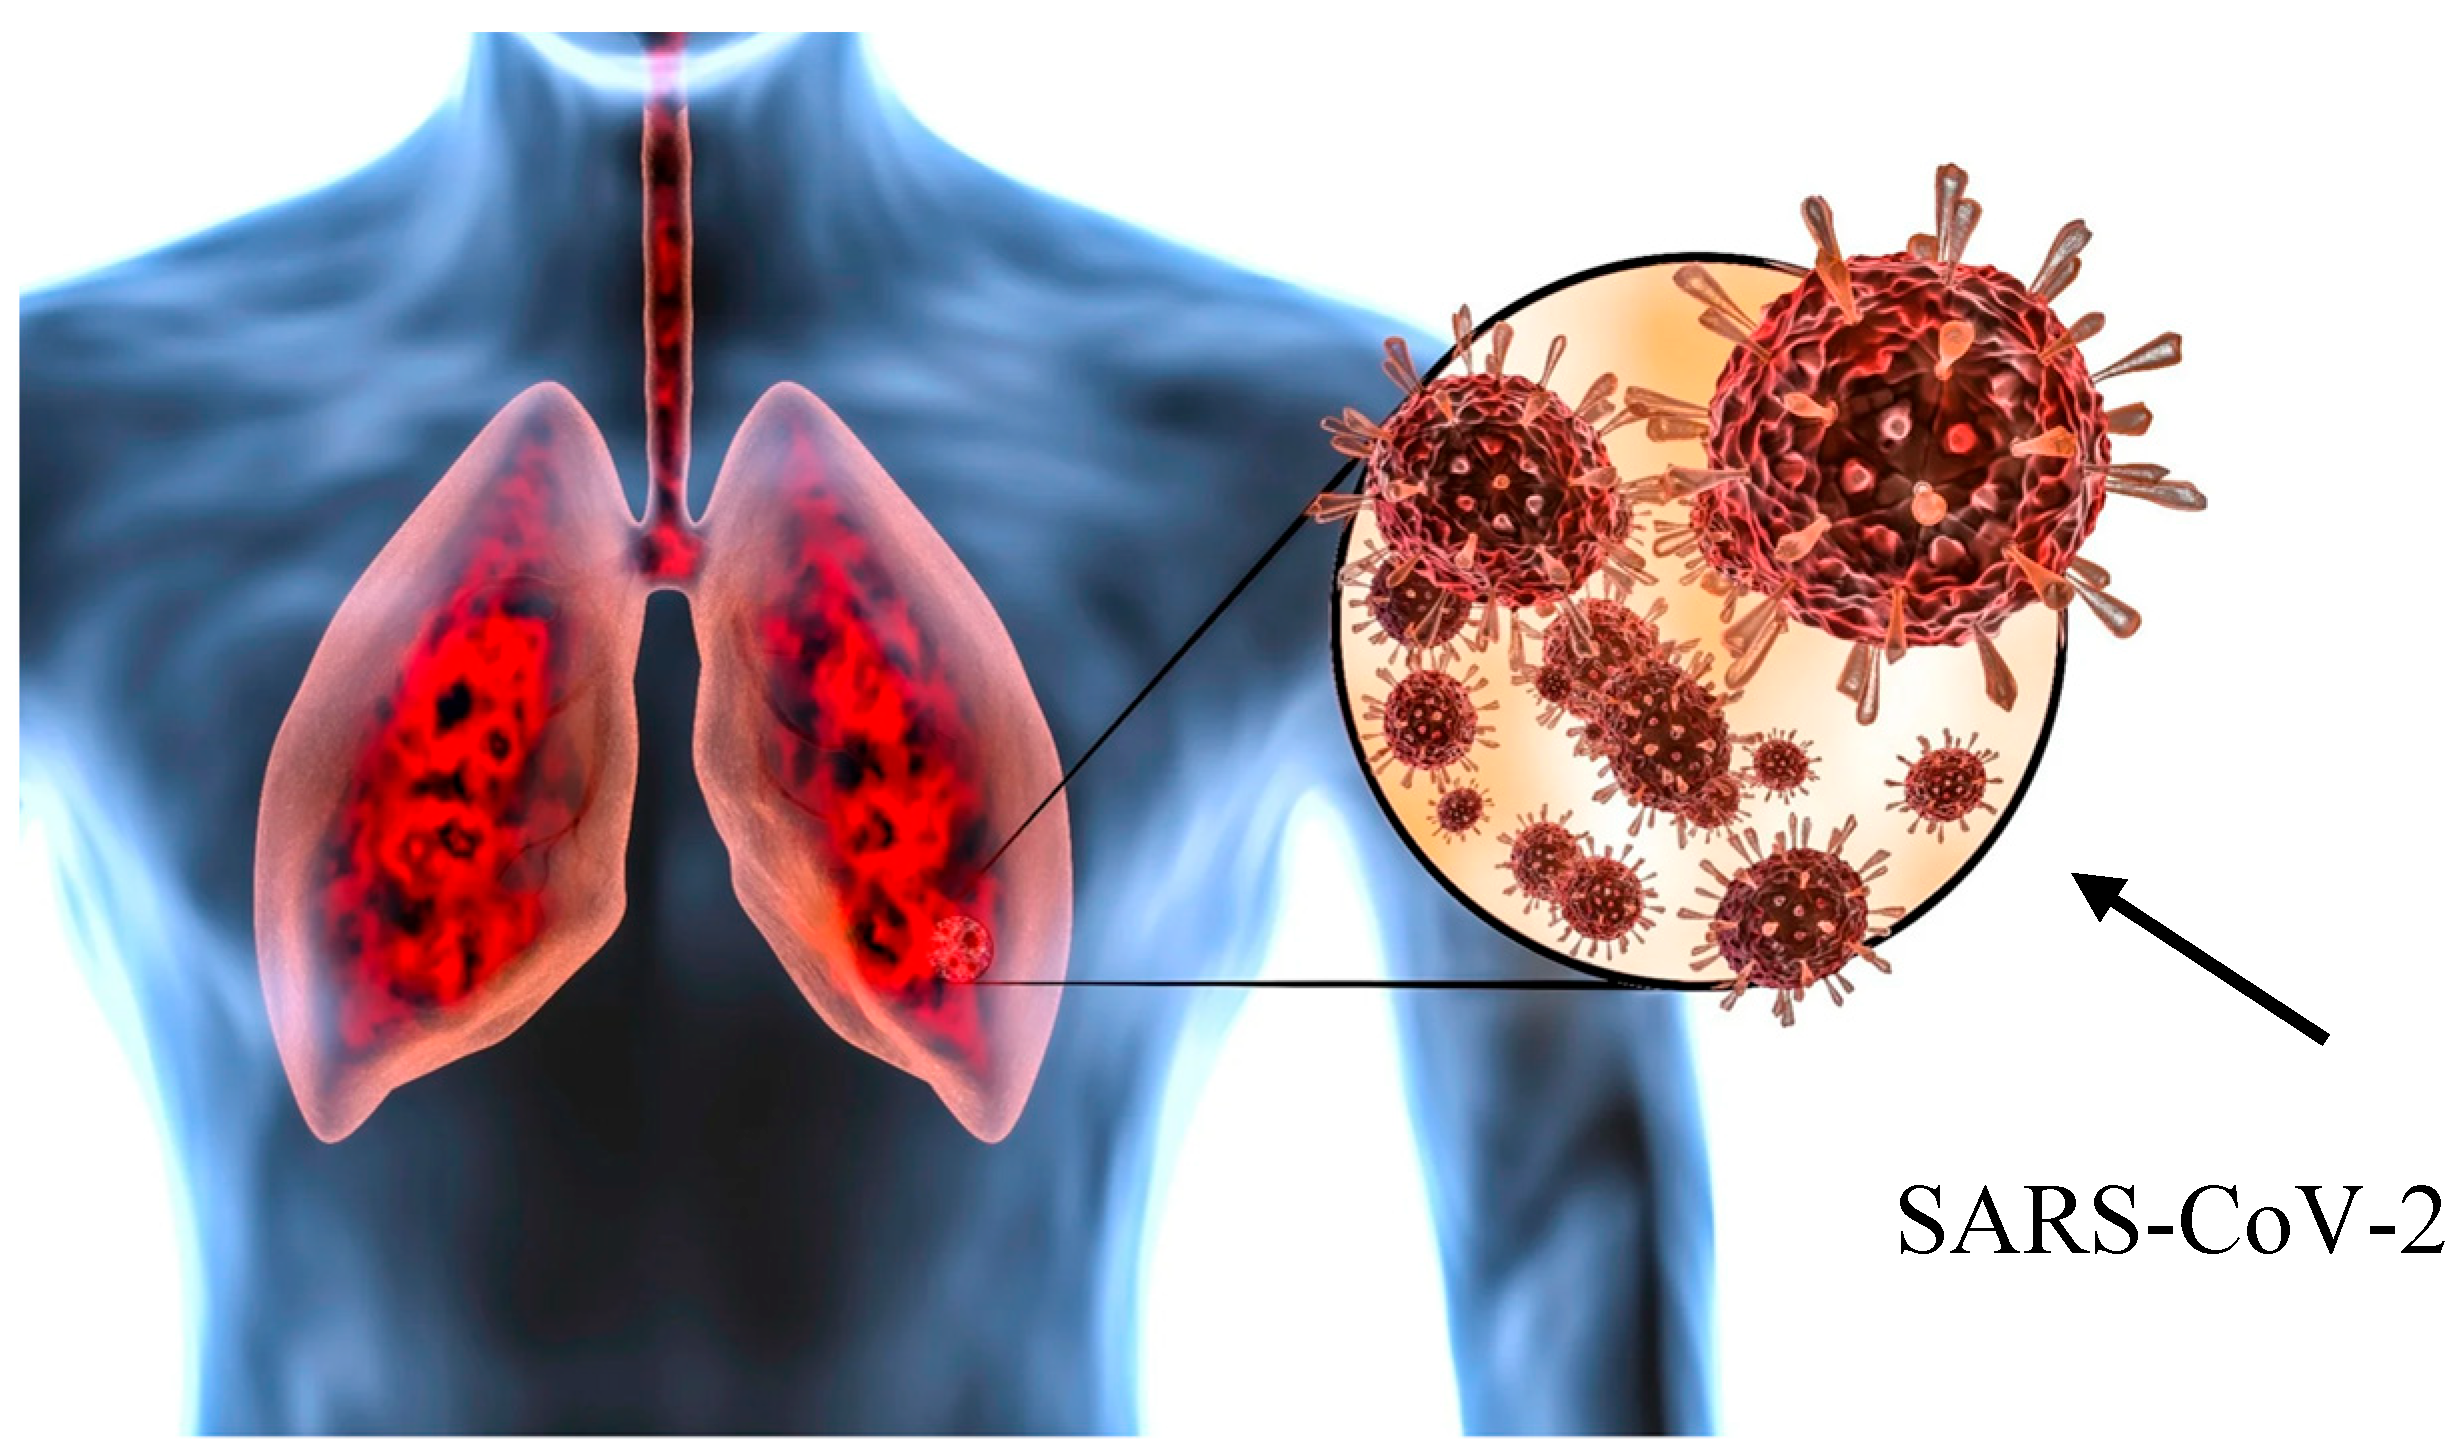

3. Pulmonary Fibrosis Mechanisms

Infection with SARS-CoV-2 triggers acute lung injury accompanied by intense alveolar inflammation. Notably, a significant proportion of COVID-19 patients develop Acute Respiratory Distress Syndrome (ARDS) leading to extensive lung injury. The lung responds to inflammatory damage by producing scar tissue (fibrosis), which replaces healthy lung tissue. The alveolar inflammatory response to SARS-CoV-2 induces excess matrix production, causing post-COVID-19 pulmonary fibrosis. However, the exact pathophysiological mechanisms of post-COVID-19 pulmonary fibrosis remain unclear, and the cause may be multi-factorial. The virus may damage the lungs directly or produce an inflammatory process leading to fibrosis. Plasma proteomics analysis identified 35 proteins closely involved in pathways associated with cell proliferation, tissue remodeling, inflammation, immune response, angiogenesis, and fibrosis. Further, García-Hidalgo et al. found that genes encoding the proteomic profile were enriched in lung epithelial, endothelial, and immune cells [3]. Proteins involved in lung fibrosis are not related to a single pathogenetic process but rather to a complex interplay between inflammation and remodeling. A dysregulated phenomenon of repair mechanisms, including fibroblasts and myofibroblasts, lead to excessive secretion of the extracellular matrix [4]. This fibrotic process occurs particularly in alveolar lung regions, leading to increased airway wall thickness and loss of alveolar tissue, resulting in ventilation–perfusion disorders and hypoxemia.